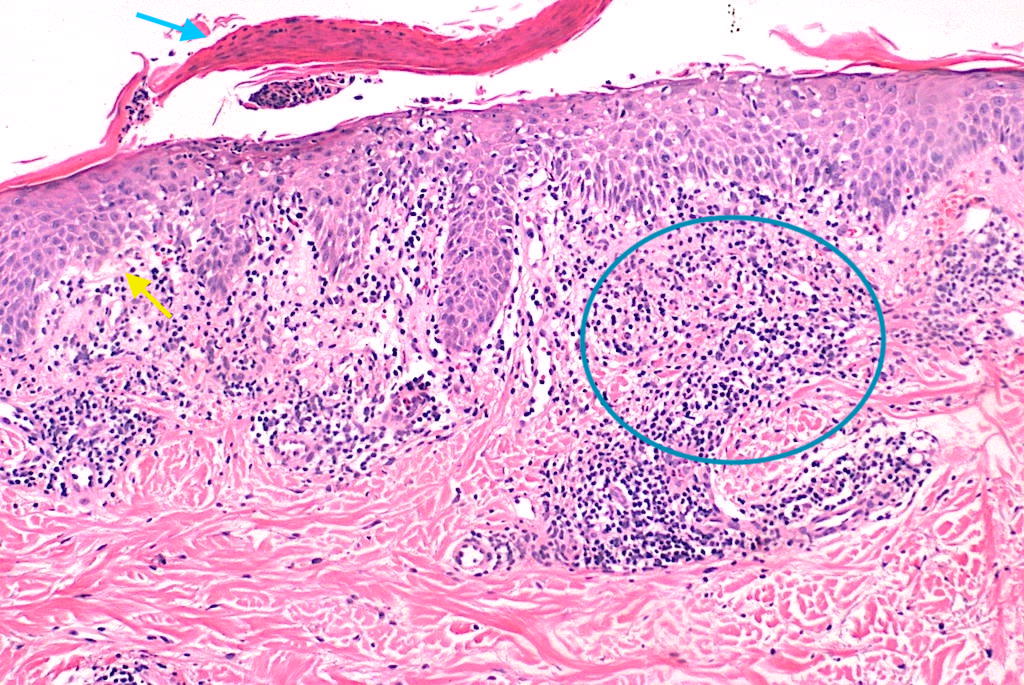

Biopsia punch 4–5 mm de lesión temprana ± costrosa con H&E; considerar segunda biopsia perilesional para IFD si dudas de vasculitis. Muhlbauer 1984.